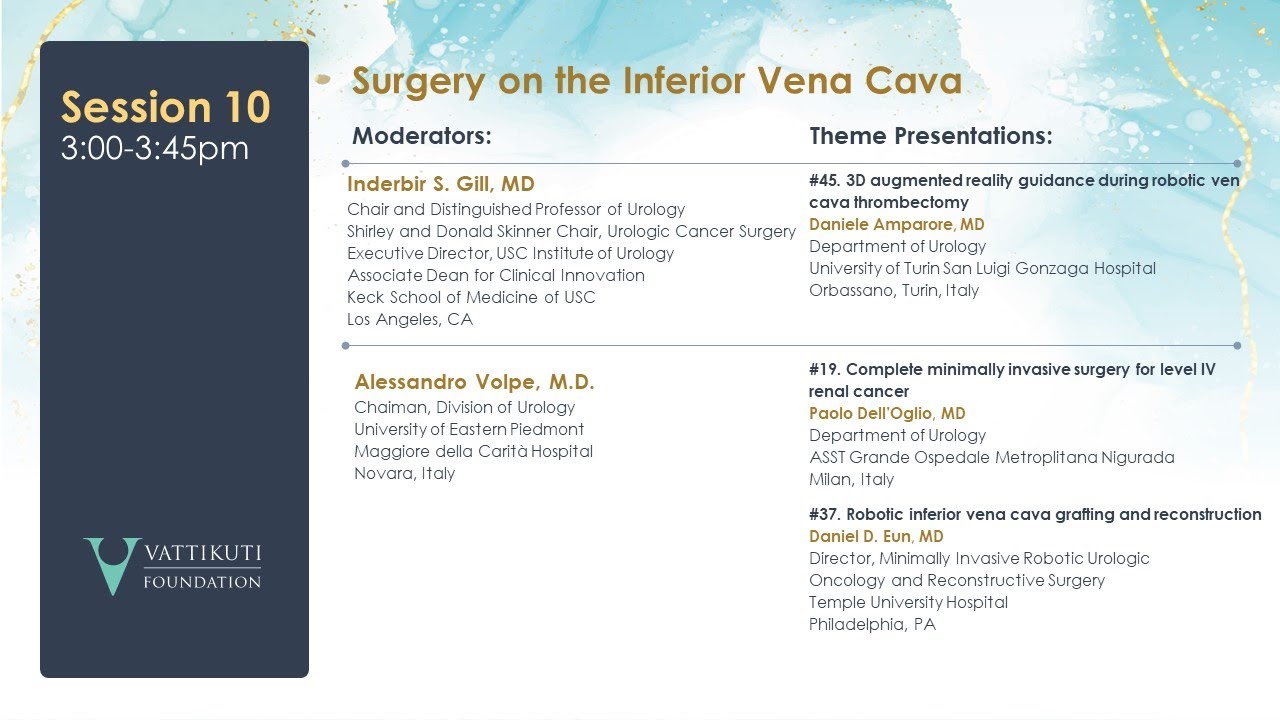

Complete minimally-invasive surgery for level IV Renal Cancer

3D augmented-reality guidance during Robotic vena cava thrombectomy

Robotic Inferior Vena Cava Grafting and Reconstruction